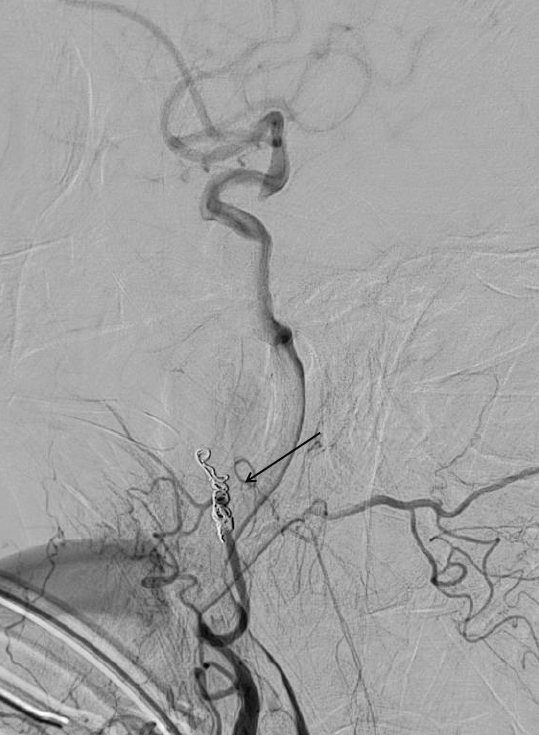

光田綜合醫院將金屬線圈(箭頭處)置放於病灶處,阻斷了病灶的血液供應,讓鼻腔不再出血。

假性動脈瘤屬於血管病變,必須從內部根源去處理病灶,由影像醫學部暨醫療副院長嚴寶勝施行「動脈血管栓塞治療術」,成功阻斷了病灶的血液供應,術後林女士復原良好,目前鼻腔不再出血,呼吸恢復順暢。沈炳宏主任提到,林女士的狀況較為特殊,是二十多年前電療引起的後遺症,多數假性動脈瘤是由外傷造成,且以腦部表現居多,這次鼻腔出血的症狀表現,在他行醫生涯中實屬罕見。